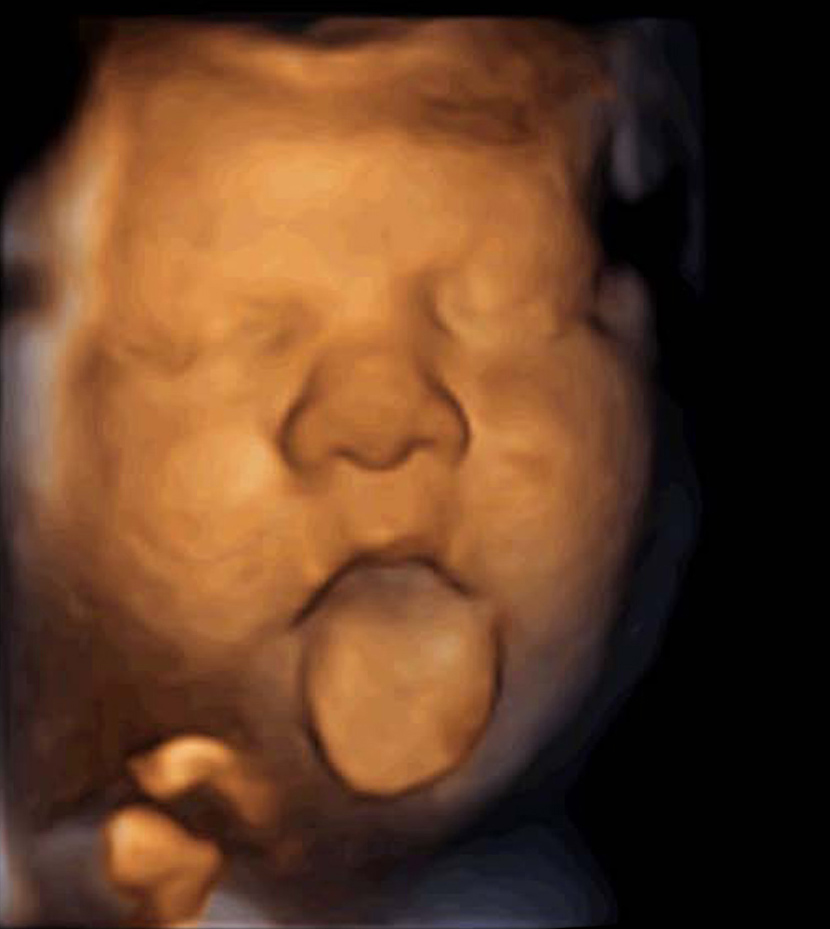

“Foetuses react with vocalisation movements when we can reach them with voice messages through their mother’s vagina. The response is different when we emit music and we put this down to music and voice activating different brain circuits: music activates neuronal circuits that trigger emotions”, says Dr. García-Faura, who has compared the differing reactions by using transabdominal ultrasounds. Accordingly, 70% of foetuses move their mouths when they are talked to; when they hear music they make more complex movements that also include the protrusion of their tongues.